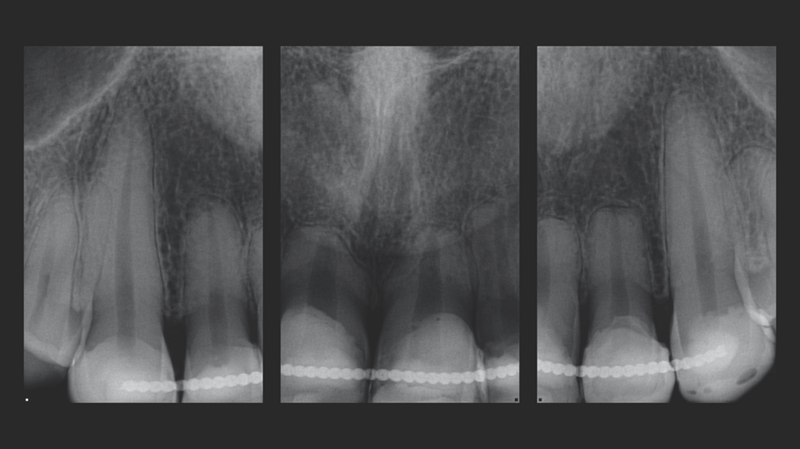

- Hintergrund des Falls: Patientin in den 20ern mit Frontzahntrauma im Oberkiefer. Die Zähne waren trotz Trauma stabil, so dass keine Implantate erforderlich waren.

Eine junge Frau in den 20ern stellte sich in der Praxis von Dr. Jaleena Fischer-Jessop, DDS, MBA, vor. Sie hatte Verfärbungen im oberen Frontzahnbereich, welche durch ein Trauma verursacht worden waren und wünschte sich eine Lösung für ein ästhetischeres Lächeln. Die Behandlung der Patientin erfolgte mit einer konservativen und kostengünstigen Lösung: direkte Non-Prep-Veneers. Dr. Fischer-Jessop entschied sich für diese Vorgehensweise, um die Verfärbung abzudecken, die oberen Frontzähne der Patientin an die unteren anzugleichen und invasivere Methoden wie Implantate oder teure, im Labor hergestellte Veneers zu umgehen. Die Farben B1D und Enamel White (EW) wurden zur Aufhellung der Zähne verwendet. Das Transcend™ Komposit (Farbe „Universal Body“, UB) sorgte für einen natürlichen Übergang zwischen den Randbereichen und den zervikalen Bereichen.